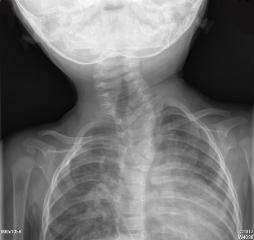

Torcicolo congênito

Imagem do vértice de uma cabeça retratando achados típicos de plagiocefalia associados ao torcicolo muscular congênito. Observe a forma típica de paralelogramo decorrente das forças de compressão externas assimétricas e do crescimento associado. *Indica o lado do músculo esternocleidomastoideo encurtado e o torcicolo resultante

Preparado pela Dra. Joyce L. Oleszek; usado com permissão